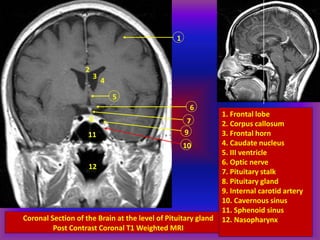

Coronal Section of the Brain at the level of Pituitary gland

Post Contrast Coronal T1 Weighted MRI

1. Frontal lobe

2. Corpus callosum

3. Frontal horn

4. Caudate nucleus

5. III ventricle

6. Optic nerve

7. Pituitary stalk

8. Pituitary gland

9. Internal carotid artery

10. Cavernous sinus

11. Sphenoid sinus

12. Nasopharynx